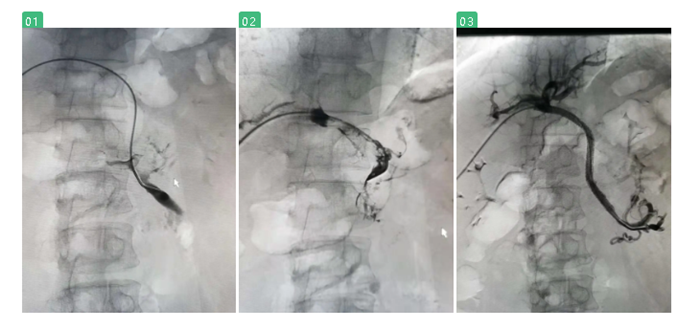

在陸煒的指導(dǎo)下,血管外科診療組長程國兵副主任醫(yī)師為江先生施行“經(jīng)皮肝穿刺門靜脈、腸系膜上靜脈造影+Angiojet吸栓+支架植入球囊擴(kuò)張術(shù)”。

經(jīng)過季肋部穿刺至門靜脈時,發(fā)現(xiàn)江先生的門靜脈及腸系膜上靜脈已完全閉塞,程國兵巧妙地引入導(dǎo)絲、放入導(dǎo)管,一點點清除門靜脈血栓,最后,成功放入支架。

術(shù)中復(fù)查造影,顯示支架定位準(zhǔn)確,展開良好,腸系膜上靜脈及門靜脈主干血流通暢。

圖一、二:血管閉塞,充滿血栓 圖三:血栓清除,恢復(fù)血流